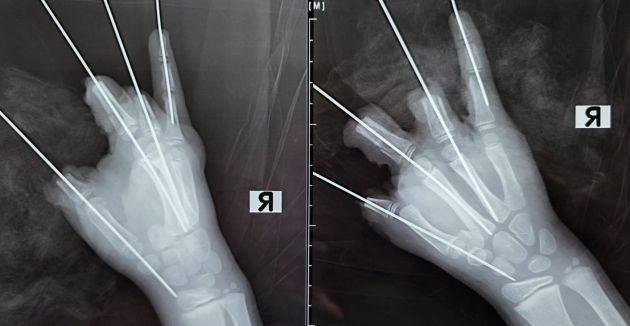

По предварительным данным, около семи вечера 11 февраля школьник находился на прогулке, когда у него в правой руке взорвалась, предположительно, петарда. Ребенок получил открытый перелом и вывих пястной кости, ампутацию четырех пальцев, повреждение мизинца с размозжением мягких тканей.

В 21:40 бригада скорой доставила пострадавшего в клинику вуза, где специалисты в течение пяти часов проводили сложную операцию с установкой металлических имплантатов.

"Мы постарались сохранить максимально возможный объем тканей. К сожалению, повреждения были очень серьезными, многие мягкие ткани были утрачены. При такой травме реконструировать конечность не представлялось возможным", – сообщил детский микрохирург Антон Волков.